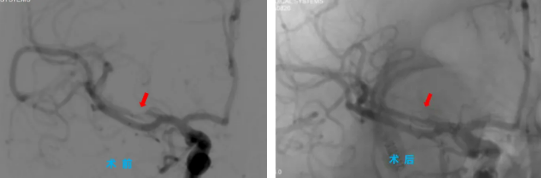

手術(shù)當(dāng)天,院長(zhǎng)助理、神經(jīng)內(nèi)科主任程偉與神經(jīng)內(nèi)科三病區(qū)副主任彭偉聯(lián)手為患者主刀,通過(guò)高難度的微創(chuàng)介入治療,成功為患者大腦中堵塞的血管進(jìn)行了球囊擴(kuò)張并置入支架,打通了“生命通道”。術(shù)后,患者手腳能活動(dòng)了,說(shuō)話(huà)也清楚了,恢復(fù)得一天比一天好,一周后,患者康復(fù)出院。